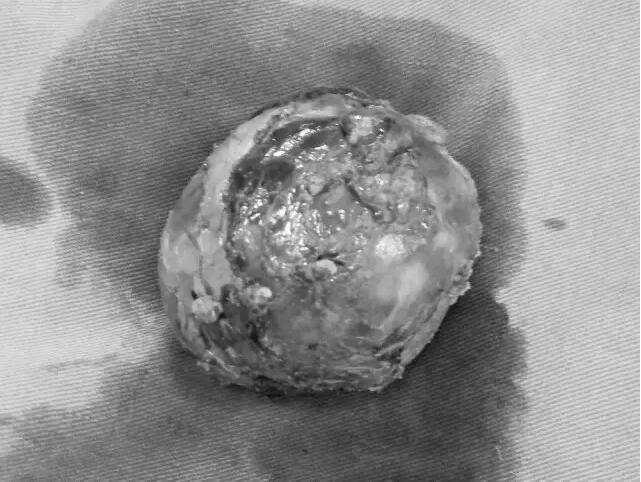

8月2日,手术在紧张有序的气氛中如期进行,术中发现肿瘤体积巨大,6cm×6cm×5cm,起源于胰头,周围与门静脉、胆总管下段及胰管关系密切,其中门静脉及胆总管明显受压并推挤移位,已经严重影响了门静脉血流及胆汁的正常排放。并且门静脉多支粗大侧支血管布满肿瘤表面,手术难度可想而知。在李晓勇主任医师、崔卫东副主任医师、陈升阳医师及张永医师的共同努力下,有麻醉科郭佩垒医师的保驾护航,历经4个小时的奋战,迎难而上,巨大肿瘤被成功切除。此时检查手术创面,发现胆总管下段、门静脉主干完全裸露,因为术中操作精细,这两个重要结构没有任何损伤。至此,手术室里紧张窒息的气氛一下子就缓和了,主任也舒展了眉头。当李主任将切除的肿瘤让莹莹妈妈查看时,莹莹妈妈更是激动地热泪盈眶。

术中照片

切除巨大瘤体